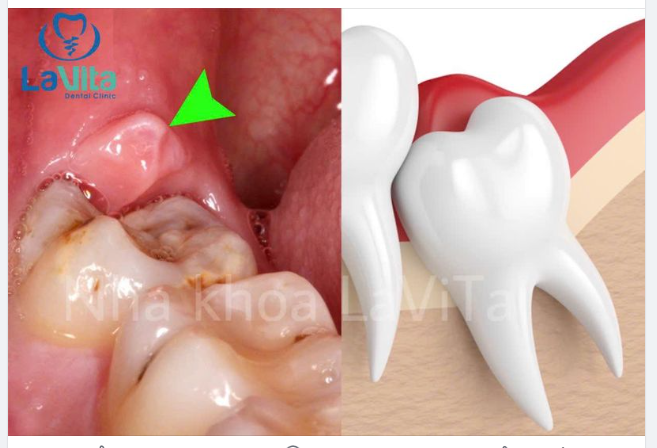

Răng khôn mọc kẹt, mọc chếch má, mọc ngang đã gây biến chứng.

Răng khôn chưa gây biến chứng nhưng có khe giắt giữa răng khôn và răng bên cạnh, sẽ sớm ảnh hưởng đến răng bên cạnh.

Răng khôn mọc thẳng, đủ chỗ, không bị cản trở nhưng hình dạng bất thường, nhỏ, dị dạng, cũng gây nhồi nhét thức ăn với răng bên cạnh, lâu dần dễ gây sâu răng và viêm nha chu răng.

Răng khôn đã bị sâu.